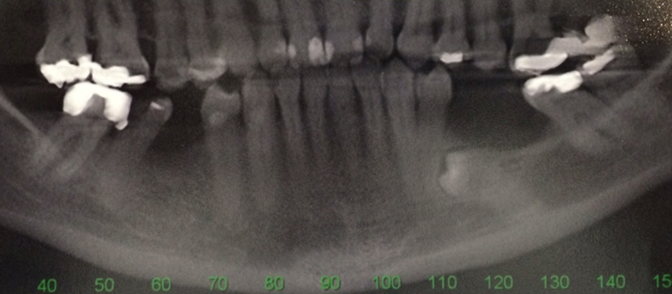

Case 1: a 37-year-old patient sought treatment with osseointegrated implants to replace a removable prosthesis in the posterior region of the mandible. In the imaging exams, a lower premolar was discovered included in the edentulous area (figure 1). After evaluation by an orthodontic specialist, traction was ruled out. In an evaluation using cone beam tomography, a close relationship was observed between the tooth and the inferior alveolar nerve from the crown to the apex, the nerve was embraced by the tooth (figure 2). When assessing the risk-benefit of tooth removal, the high chance of paresthesia was considered, in addition to a probable large height defect after tooth extraction.

Figure 1: Panoramic radiograph showing an impacted premolar in an edentulous area (third quadrant).